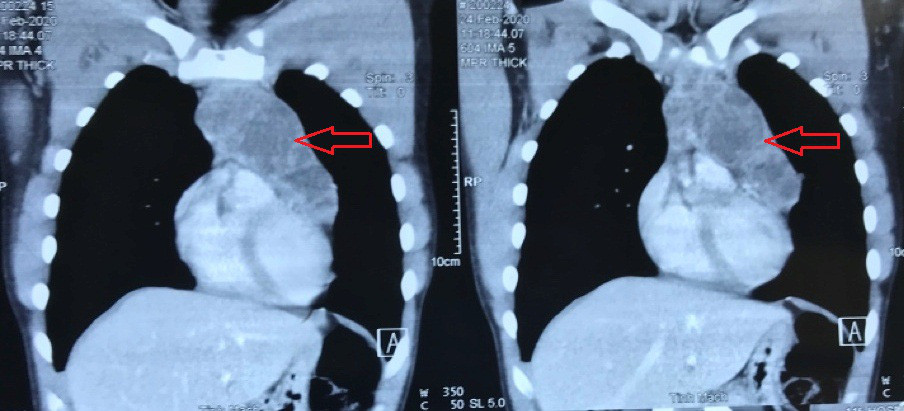

Nhập viện Bệnh viện Nhân dân 115, bác sĩ chỉ ghi nhận bệnh nhân than đau ngực nhẹ, ngoài ra không có triệu chứng gì bất thường. Qua CT scan ngực vùng trung thất cho thấy hình dạng khối u kích thước khoảng 8.5 x 8 x 6 cm. Các bác sĩ tiến hành mở ngực trái và bóc ra khối u to có kích thước 10x10 cm, nặng 1 kg, xâm lấn, chèn ép động mạch chủ, tĩnh mạch chủ.

Khối u khổng lồ trong lồng ngực bệnh nhân (Ảnh: Do BV Nhân dân 115 cung cấp)